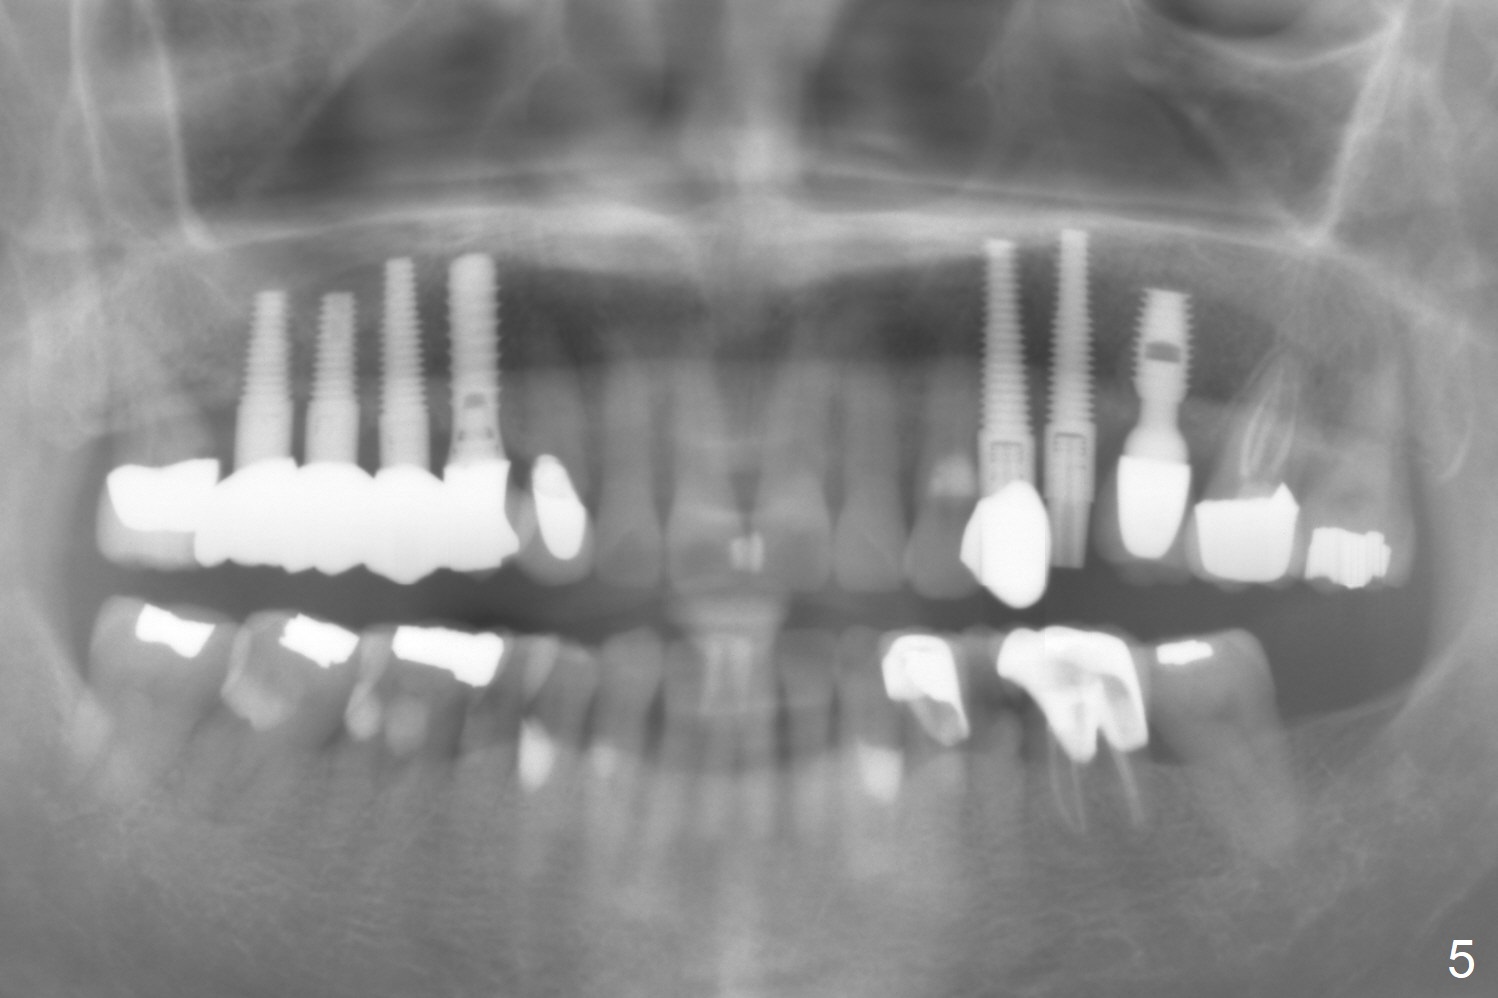

The root of the tooth #13 has an oblique fracture as related to a prefabricated post after 9 years of service (Fig.1). The trajectory of the initial osteotomy (Fig.2) is corrected with Lindamann bur and reuse of 2 mm drill (Fig.3). A 4x20 mm tissue-level implant is placed with > 60 Ncm, followed by tightening a 3.5x5 mm abutment (Fig.4,5); the mesiobuccal defect being filled with Vera Graft (Fig.4 *). An immediate provisional is fabricated. It appears that the implant should have been placed deeper (Fig.6: 5 months postop).